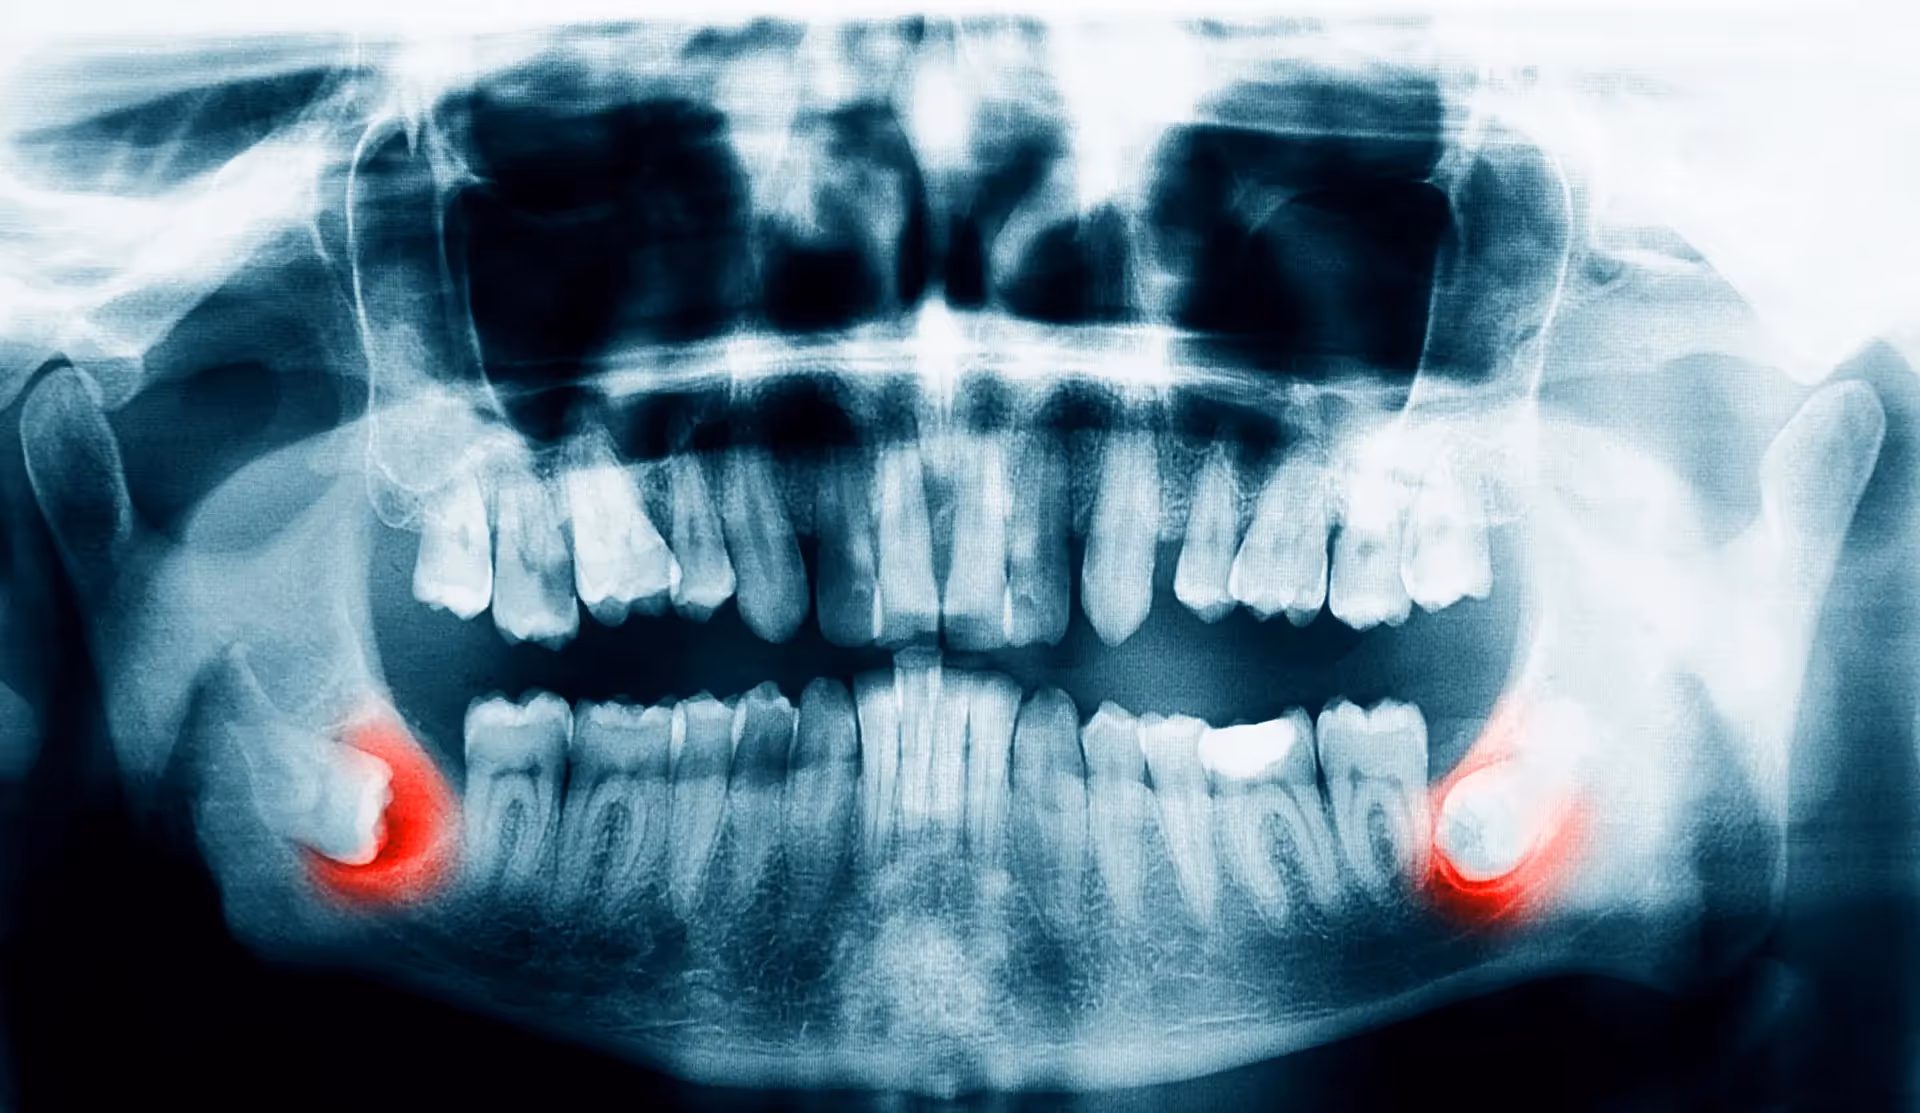

Wisdom teeth often have to be extracted to ensure the rest of your teeth stay healthy. Most wisdom teeth erupt misaligned, which can cause tooth crowding and disruption in your teeth and gums. This is not only painful but can make oral hygiene more difficult. Another common reason for wisdom teeth extraction is a partial eruption. This encourages bacteria to accumulate in the pockets of your gums, putting you at risk for gum disease, infection, and tooth decay. That being said, sometimes wisdom teeth don’t always need to be removed. If your wisdom teeth erupt properly aligned and don’t impact your other teeth, your doctor may not recommend extraction. But generally, wisdom teeth need to be removed to preserve a healthy smile.